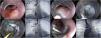

One week after clip placement, the patient presented with hemoptysis on 2 occasions, as well as fever. Endoscopic examination revealed that the OVESCO clip had partially migrated, and so it was removed. Persistence of the fistula with a 2 mm diameter was confirmed. Endoscopic closure combining the ESD technique and hemoclip application was decided upon. To carry it out, a submucosal injection 3 mm proximal to the ERF was applied, enabling the dissection of an approximately 10 mm circumferential area, with an I knife (ERBE, Tübingen, Germany). Once the ERF was denuded and isolated, passage of contrast medium into the right bronchopulmonary region, utilizing a 0.035″ guidewire (Jagwire™, Boston Scientific, Marlborough, MA, USA), was confirmed. Fistulectomy was performed, using Endocut mode I in effect 3, to eliminate the fistulous epithelium, at an approximate depth of 5 mm in that region. Closure was satisfactorily carried out with 3 hemoclips and confirmed through contrast medium instillation (Fig. 1).

Esophagobronchial fistula closure technique with endoscopic submucosal dissection combined with hemoclips. A) Persistence of the fistula after removal of the OVESCO T clip, 22 cm from the superior dental arch. B) Confirmation of the fistula through contrast medium injection. C) Start of the dissection, with submucosal injection 3 mm proximal to the fistula. D) Complete endoscopic fistulectomy, including dissection at the level of the muscularis propria of the esophagus. E) Passage of the guidewire through the fistula. F) Fluoroscopic image showing the guidewire in the bronchopulmonary region. G) Placement of 3 hemoclips for definitive closure. H) Contrast medium instillation confirming complete closure of the fistula and no signs of contrast medium passage into the bronchial region.